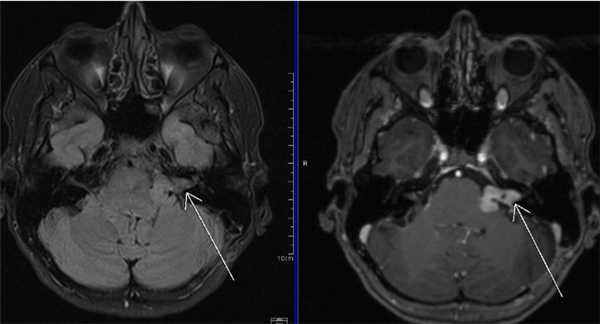

МРТ головного мозга. На мрт в аксиальной плоскости отмечается объемное образование внутреннего слухового прохода слева (стрелка), с четкими и неровными контурами, деформирующее окружающие структуры. После внутривенного введения парамагнитного контрастного вещества отмечается интенсивное и неоднородное его накопление образованием (изображение справа) — невринома.

Вестибулокохлеарный нерв (VIII) состоит из 4 пучков. Опухоли происходят обычно из вестибулярной его части. Шваннома - инкапсулированная доброкачественная (градация 1) опухоль, происходящая из дифференцированных неопластических шванновских клеток оболочек периферических нервов. Невриномы ММУ составляют около 3% опухолей головного мозга. Часть шванном (двухсторонние слуховых нервов) связана с НФ 2 типа. Пик частоты между 40 и 60 годами. Растут медленно и крайне редко малигнизируются. Клинические проявления связаны с нарушением функции нерва и компрессией ствола. Шваннома может происходить из любого отрезка по ходу нерва и хорошо прослеживается при МРТ области ММУ. Невринома видна как на Т2-взвешенных, так и на Т1-взвешенных МРТ в виде округлого образования. Невриномы хорошо и равномерно усиливаются после МРТ с введением контрастного вещества. Невриномы области цистерны могут иметь компонент во внутреннем слуховом проходе, особенно, хорошо видимый при МРТ головного мозга с контрастированием. Изредка встречаются невриномы полностью расположенные внутри канальца. Они составляют наибольшую диагностическую сложность при МРТ, требуют тонких срезов и контрастирования. Менингиомы ММУ обычно типично расположены и при МРТ имеют характерную форму и типичные черты при МРТ с контрастированием. Однако редко встречаются внутриканальцевые менингиомы. При МРТ они неотличимы от неврином. Холестеатомы при МРТ имеют смешанную интенсивность сигнала, в зависимости от их содержимого. На диффузионно-взвешенных МРТ холестеатомы обычно яркие.